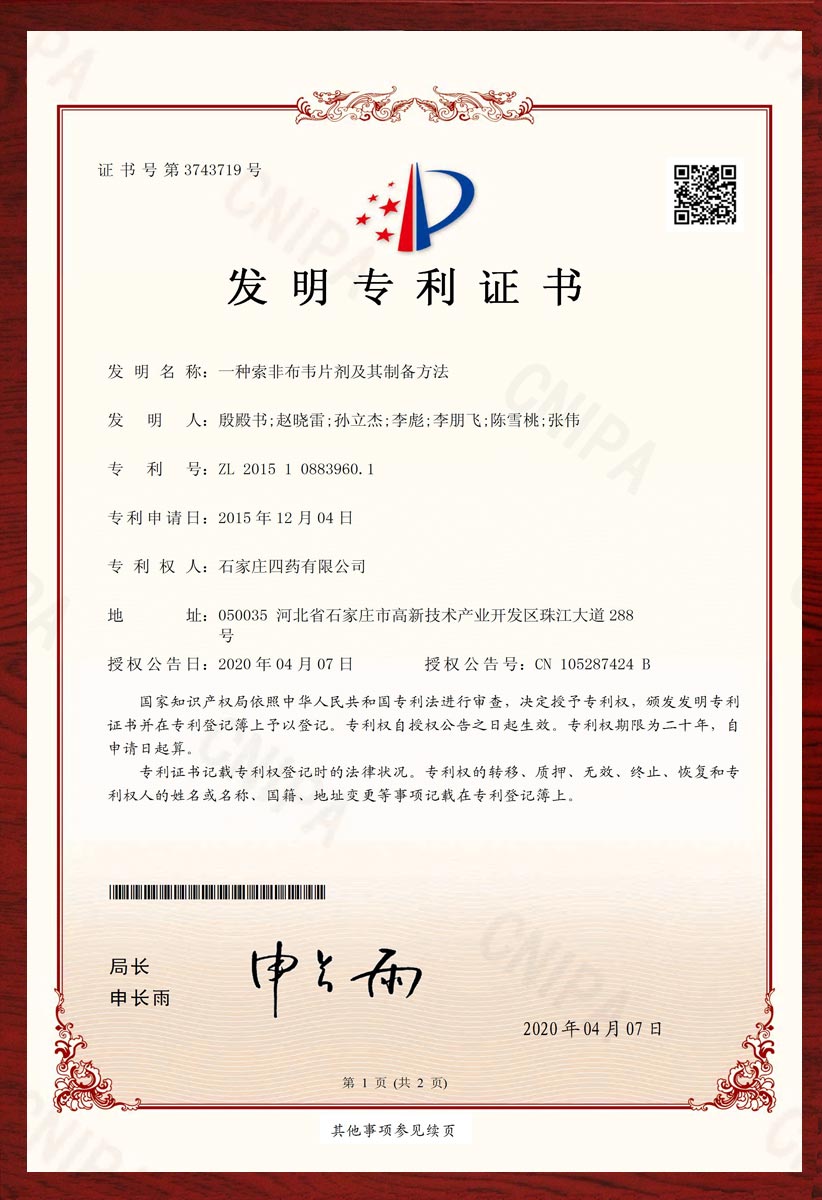

专利证书